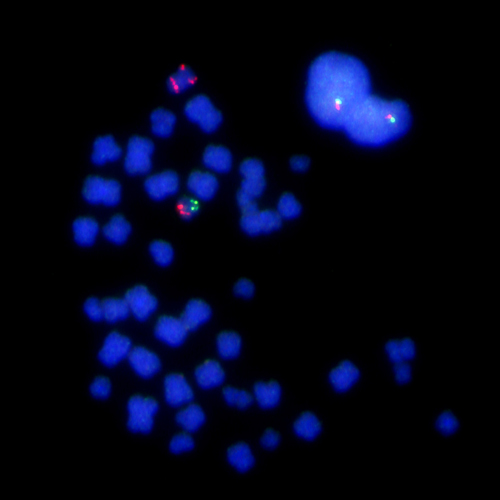

KBI-10105

ON 6q21 / SE 6